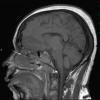

Mucormycosis - Zygomycosis